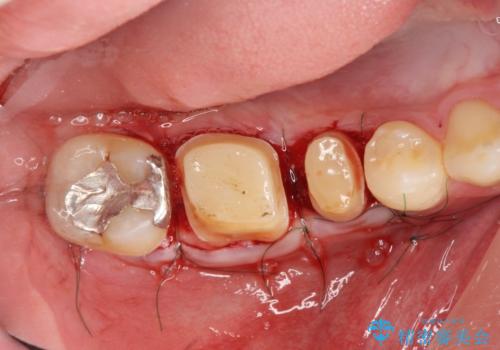

歯周組織が落ち着くのを待ち、セラミッククラウンで機能・審美性を改善します。

- 37.4万円(ジルコニアクラウン×2・仮歯×2・歯周外科)費用は治療当時の料金となります

歯内・歯周環境が整備されたことで長期的な予後の期待できるセラミック治療を行うことができました。